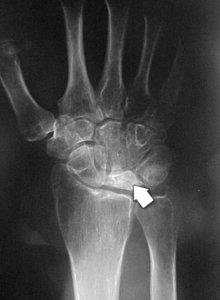

Popular topics On the part of the bodyFeaturedPatellofemoral Pain syndrome Broken neck fracture (broken collar)Public themes by the body Knee ArthroscopyTotal Hip ReplacementPopular Thematics By Part of the Body Activities After Kneeator Cuff and Shoulder Conditioning ProgramPopular Themes By BodyFeoneturedA Safety Guide Your best health. Diseases " Highlights Treatment of Popular Themes Popular Theme Recovery Popular Themes Maintain HealthyFeaturesPopulers PrintEmailFacebookTwitterKienböck's DiseaseKenböck's disease is a condition where the blood supply is interrupted to one of the small bones of the wrist, the lunatic. The bone is living tissue that requires a regular supply of blood to nourish. If the blood supply to a bone stops, the bone can die. This is called osteonecrosis. The damage to the lunatic causes a painful and rigid wrist and, over time, can lead to arthritis. Because the cause of Kienböck's disease is not known. Many people with Kienböck's disease think they have a sprained wrist at first. They may have experienced some form of wrist trauma, like a fall. This type of trauma can interrupt blood flow to the lunatic. Some things may put you at greater risk for the disease. For example, most people have two glasses that supply blood to the lunatic, but in some people there is only one source. This can delay blood flow to the bone. Also, if the two bones of the forearm (the radio and ulna) are different lengths, you can press extra to the lunatic during some wrist movements. Over time, this extra stress on the bone can lead to Kienböck disease. SymptomsThe most common symptoms of Kienböck's disease include: Medical Exam Kienböck's disease is a condition that progresses slowly, and many people don't decide to see a doctor until they have experienced symptoms for several months, perhaps more. During your first appointment, your doctor will discuss your symptoms and medical history, and then examine your hand and wrist. In its early stages, Kienböck disease may be difficult for your doctor to diagnose because the symptoms are so similar to those of a sprained wrist. Imaging tests, such as X-rays and MRI images, are used to confirm a diagnosis of Kienböck disease. Kienböck disease progresses through four stages of gravity. If you are diagnosed with Kienböck disease, your doctor will plan your treatment based on several factors, which is more important, the stage of your progression. Stage 1During the first stage of the disease, the symptoms are similar to those of a wrist sprain. Although the blood supply to the lunatic has been interrupted, X-rays may appear normal or suggest a possible fracture. An MRI analysis can better detect blood flow and is useful for making diagnosis at this early stage. Stage 2The lunar bone begins to harden due to lack of blood supply during Stage 2. This hardening process is called sclerosis. In addition, the lunatic will appear brighter or whiter in X-ray areas, indicating that the bone is dying. To better assess the condition of the lunatic, your doctor may also order MRI scanners or CT scans. The most common symptoms during this stage are wrist pain, inflammation and sensitivity. Stage 3In the third stage, the dead lunar bone begins to collapse and break into pieces. As the bone begins to break, the surrounding bones can begin to change the position. During this stage, patients often experience growing pain, weakness in grip and limited wrist movement. Stage 4If the condition progresses to Stage 4, the surfaces of the bones surrounding the lunatic also deteriorate, and the wrist can become arthritic. Treatment Although there is no complete cure for Kienböck disease, there are several non-surgical and surgical options to treat it. Treatment goals are to relieve pressure on the lunatic and try to restore blood flow inside the bone. Related Articles Wrist Arthritis Wrist Sprains Non-surgical Treatment In the very early stage of the disease, pain and inflammation can be given with anti-inflammatory drugs, such as aspirin or ibuprofen. Doll immobilization for a period of time can help relieve pressure on the lunatic, and your doctor may recommend spine or casting for 2 to 3 weeks. It is important to monitor any changes in your symptoms during the early stage of Kienböck disease. If the pain is not relieved with simple treatments or returns, the doctor may recommend surgery. Surgical Treatment There are several surgical options to treat Kienböck disease. The choice of the procedure will depend on several factors, in particular to what extent the disease has progressed. Additional factors to consider are the patient's level of activity, personal objectives and the surgeon's experience with the procedures. Revascularization. In some cases, it may be possible to return the blood supply to the lunar bone. This procedure is called revascularization. It is more successful during the early stages of the disease—stages 1 and 2—before the lunatic has deteriorated significantly. Revascularization involves the removal of a portion of bone with attached blood vessels from another bone — most of the time a bone from the forearm (radius) or an adjacent bone in the hand. This piece of bone with its blood supply is called vascularized graft. It is inserted into the lunar bone. To help the bones remain in place during healing, an external fixer can be temporarily applied. This is a metallic device attached to the outside of the wrist with nails inserted into the bones. It can relieve pressure on the lunatic while the graft is healing and restoring a blood supply. Joint leveling. If the two bones of the lower arm are not of the same length, a joint leveling procedure may be recommended. Bones can be made longer using bone grafts or shortened by removing a section of the bone. This leveling procedure reduces the forces that compress the lunatic and often stops the progression of the disease. Approximate line spectomy. If the lunatic collapses severely or breaks into pieces, it can be eliminated. In this procedure, the two bones on each side of the lunatic are also eliminated. This procedure, called proximal row carpectomy, will relieve pain while maintaining partial wrist movement. (Left) The three wrist bones that are removed in a proximal row carpectomy are shaded here. (Right) An X-ray image of a wrist after a proximal row carpectomy. Fusion. To relieve pressure on the lunatic, the nearby bones of the wrist can be merged together to make a solid bone. A fusion can be partial, in which only some of the bones are merged. This procedure relieves pain and retains some wrist movement. If the disease has progressed to severe wrist arthritis, fusing all wrist bones to the radio will relieve pain and improve the hand function. Although the whole wrist movement is eliminated in a complete fusion, the rotation of the forearm is preserved. In a fusion, the bones of the wrist are held along with a plate, screws and pins. ResultsThe disease of Kienböck varies considerably in its severity, as well as its rate of progression. Each patient's response to treatment depends on the degree of damage to the bones of the lunar and surrounding wrist. Some patients may require more than one procedure if the disease continues to progress. In short, patients with Kienböck disease should not expect to return to normal wrist function after any treatment. However, treatment provides the greatest opportunity for long-term preservation of function and pain relief. Last revision May 2012 Contributed Updated byPeer-Reviewed byAAOS does not support any treatment, procedures, products or doctors referred here. This information is provided as an educational service and is not intended to provide medical advice. Anyone looking for specific orthopedic advice or assistance should consult your orthopedic surgeon, or locate one in your area through the AAOS program on this website. Copyright ©1995-2021 by the American Academy of Orthopaedic Surgeons. All material on this website is protected by copyright. All rights reserved. This website also contains copyrighted material by third parties.